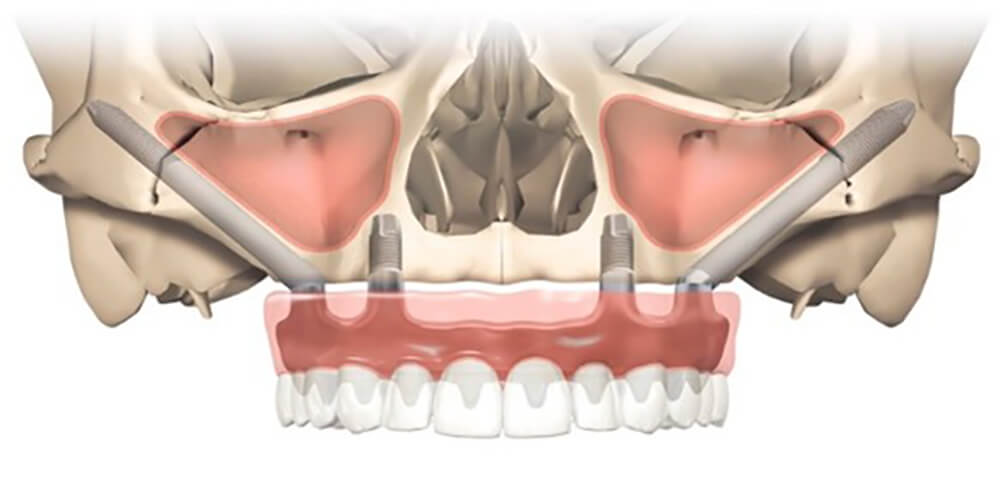

既然 All-on-4 全口重建需在口腔顎骨植入植體,萬一骨頭不夠堅固怎麼辦?

別擔心!法夏爾口腔智慧醫療團隊的醫師會為患者做完整評估,當上顎骨質流失或缺損使得植牙困難,就會建議採用 Zygoma 顴骨植體。這次 All-on-4 全口重建案例盤先生的手術,也有透過 Zygoma 顴骨植體以確保全口重建獲得最佳支撐力與穩定性。(延伸閱讀:【顴骨植體】骨頭不好無法做All-on-4全口重建? Zygoma implant 顴骨植體有解!)

顴骨是顏面主要支架,骨質密度高且強壯,不易隨著時間流失,足以提供植體良好穩定性。一般植體的長度約在 8 到 13 毫米左右,而顴骨植體的長度一般會超過 35 毫米,甚至達到50毫米,透過更長更強壯的植體,跨過萎縮骨質區,以顴骨固定植體,使上顎骨基底喪失的患者也能獲得妥善治療。